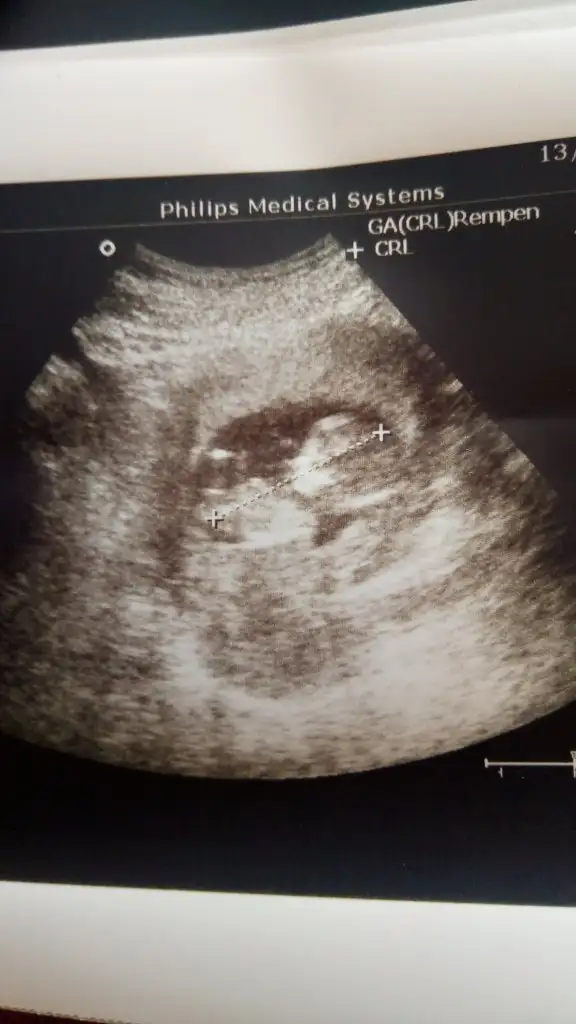

Merhaba 12 haftalik ultrason goruntusuu sizce kizmi erkekmi😍😍

Eklentiler

• 293A0F8B-6F8A-4C40-A8FF-886504904C2A.webp

293A0F8B-6F8A-4C40-A8FF-886504904C2A.webp

19,5 KB · Görüntüleme: 68